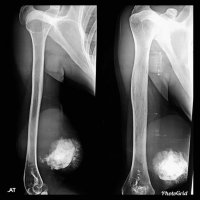

EXTRASKELETAL OSTEOSARCOMA

Extraskeletal Osteosarcoma is a rare mesenchymal malignant tumor that occurs in the retroperitoneum and soft tissue of extremities without any attachment to bone.

Most commonly occuring in individuals 40 to 80 years of age and male are more affected than females.

ESOS appears as soft tissue density with a variable amount of calcification which represents osteoid matrix formation, and is seen in -50% of cases.

Metastasis and local recurrence are quite common with ESOS, and this tumor is also insensitive to chemotherapy and radiotherapy.

The initial treatment strategy favors wide local excision of a primary tumor, including limb salvage surgery for extraskeletal osteosarcoma of the extremity.